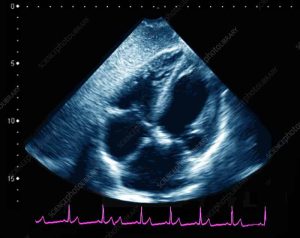

اکوکاردیوگرافی قلب چیست و چه کاربردی دارد؟ اکوکاردیو گرافی :دستگاه اکوکاردیوگرام از امواج اولتراسوند یا امواج صوتی بی ضرر استفاده می کند. متخصصین برای تشخیص اندازه، شکل و عملکرد قلب